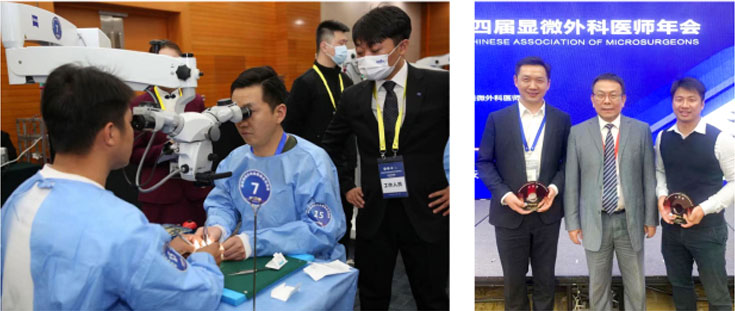

2021��7��2�գ����й�ҽʦЭ������������ҽʦ����ϣ���������һ����С������Я�ִ����������ƹ��������βμӡ�ȫ��������Ѫ���Ǻϴ��������ٻ����Ƚ���

2023��3��3��-5�գ����й�ҽʦЭ����Ľ������ҽʦ����ϣ���������һ����С�����Ρ�������ҽʦ�Ծ�տ�ļ����ٻ�ȫ��������Ѫ���Ǻϴ��������Ƚ���